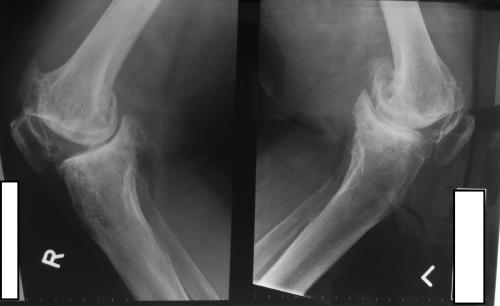

Knee Arthritis

Osteoarthritis is the most common form of knee arthritis. It is a degenerative, "wear-and-tear" type of arthritis that occurs most often in people 50 years of age and older, but may occur in younger people, too.

In osteoarthritis, the cartilage in the knee joint gradually wears away. As the cartilage wears away, it becomes frayed and rough, and the protective space between the bones decreases. This can result in bone rubbing on bone, and produce painful bone spurs.